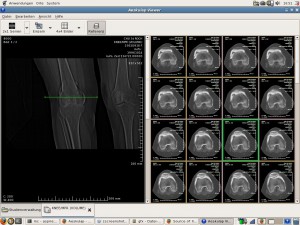

• Aeskulap: Visor de imaxes médicas e DICOM.

• CTSim: Simulador tomográfico interactivo.